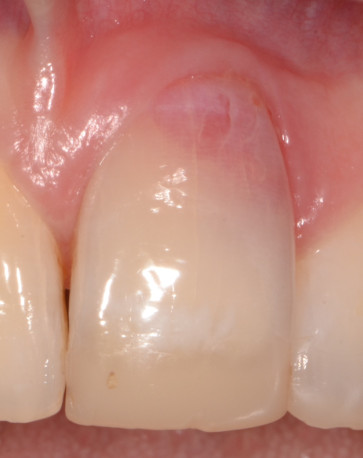

L’estetica e’ un aspetto fondamentale per qualunque trattamento odontoiatrico. Gli impianti nelle zone estetiche rappresentano oggi una delle maggiori sfide cliniche ed il successo in tali situazioni e’ frutto della cura di numerosi dettagli in ogni fase di trattamento. Nell’ambito del corso verranno illustrati i criteri di selezione delle procedure chirurgiche volte ad ottenere il successo e le tecniche di esecuzione delle stesse. Nello stesso modo verranno trattate le modalita’ di recupero estetico in quei casi dove si siano avute complicanze o fallimenti in tal senso.

• Innesto di tessuto connettivo per correzione estetica intorno a corone su impianti